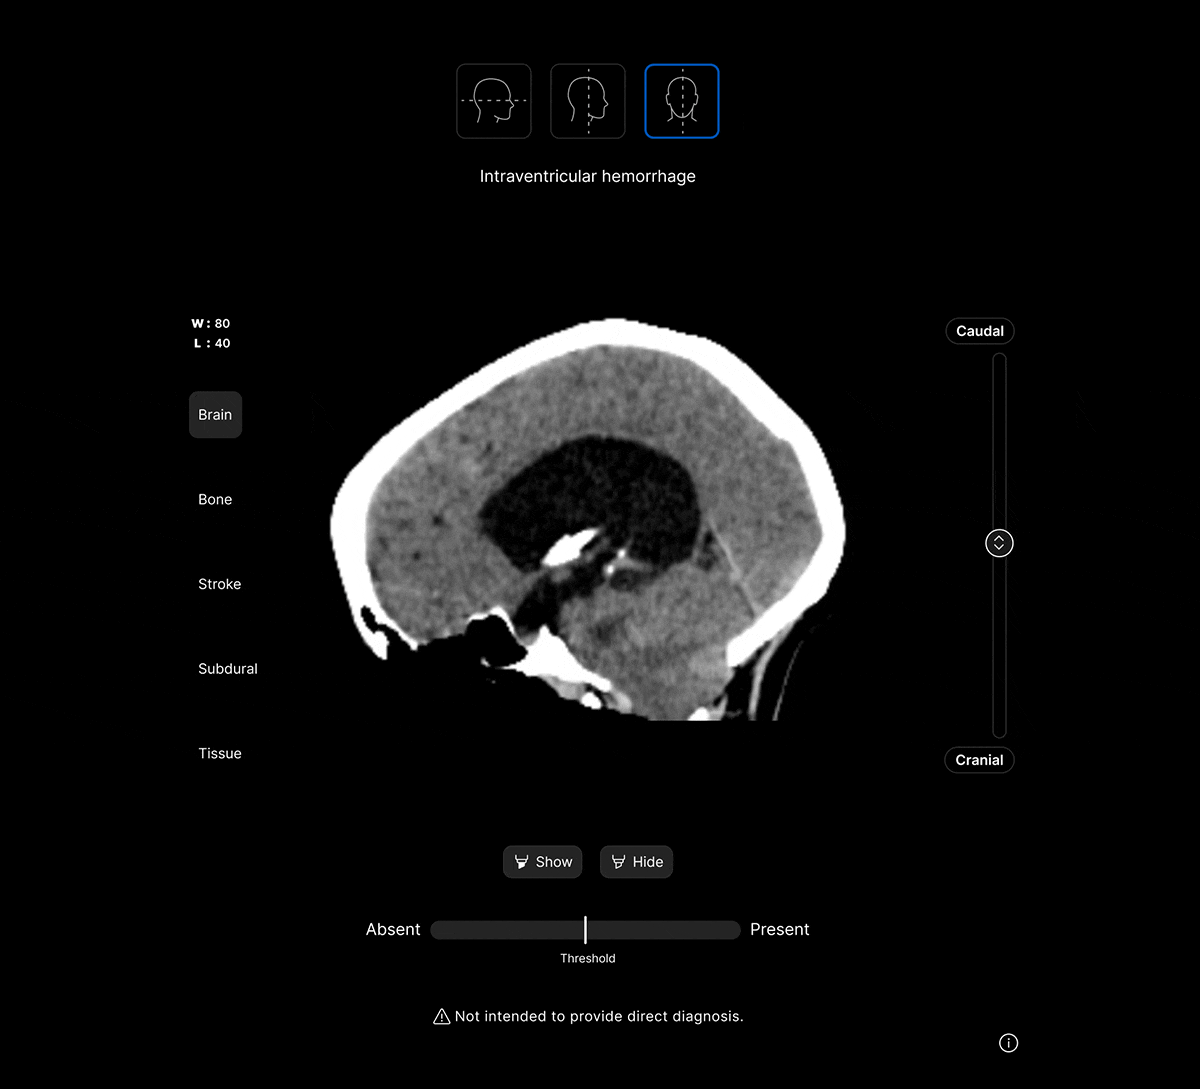

The UI integrates seamlessly with PACS/ RIS, displaying a resizable, no-click overlay window with findings and localisation.

Customisable features.

Customisable thresholds, for individual findings (to optimise for sensitivity / specificity) to tailor the workflow to your clinical setting or population.

Identifies up to 130 suspected head CT findings, grouped by urgency or other customisable criteria.

Coloured overlays on the image to quickly locate findings.

Explainable AI feature to improve AI interpretability and improve clinical decision-making.

AI analysis viewable on different head CT slices.

View the findings in sagittal, axial and coronal projections.

View findings within preset subdural, bone, brain, soft tissue and stroke views to provide additional context to the AI results.